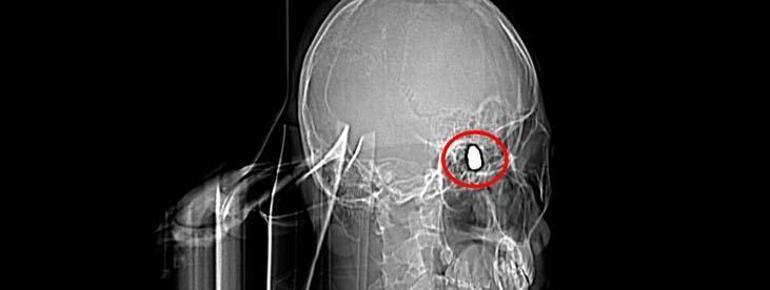

Olay, 5 Kasım 2023’te Bahçelievler Mahallesi 1624’üncü Sokak’ta meydana geldi. Arkadaşları ve ağabeyiyle maça gitmek için konutundan çıkan Yusuf Emre Özbek, birlikte fotoğraf çektirdikten çabucak sonra yere yığıldı. Etraftakilerin hastaneye götürdüğü Yusuf’un çekilen röntgeninde, başında mermi çekirdeği olduğu tespit edildi.

4 gün ağır bakım, 4 gün de serviste tedavi gören Yusuf’un başındaki mermi için hekimler, riskli bölgede olduğu gerekçesiyle müdahale etmedi. Nizamlı olarak denetim edilen Yusuf’ta konuşma zahmeti ve sağ el ve parmaklarında zayıflık belirtileri ortaya çıkınca, fizik tedavi süreci başladı.